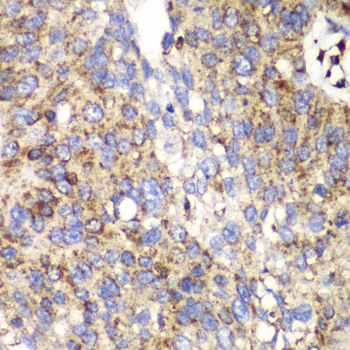

Immunohistochemistry of paraffin-embedded human lung cancer using SPARC antibody at dilution of 1:100 (400x lens).